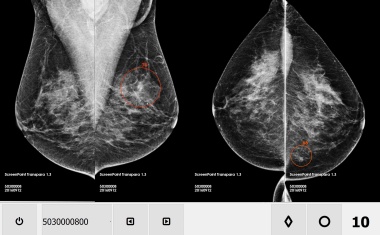

Lungentumoren aus dem Labor: Testobjekte für maßgeschneiderte Krebstherapien?

Lungenkrebs ist sehr unterschiedlich, was die Behandlung erschwert. Forscher des BIH an der Charité haben ein Verfahren entwickelt, bei dem Mini-Tumoren aus Patientenproben gezüchtet und verschiedene Therapien getestet werden.